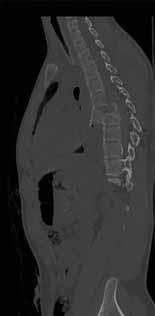

Rycina 70.5.

Rycina 70.6.

Rycina 70.7.

Rycina 70.8.